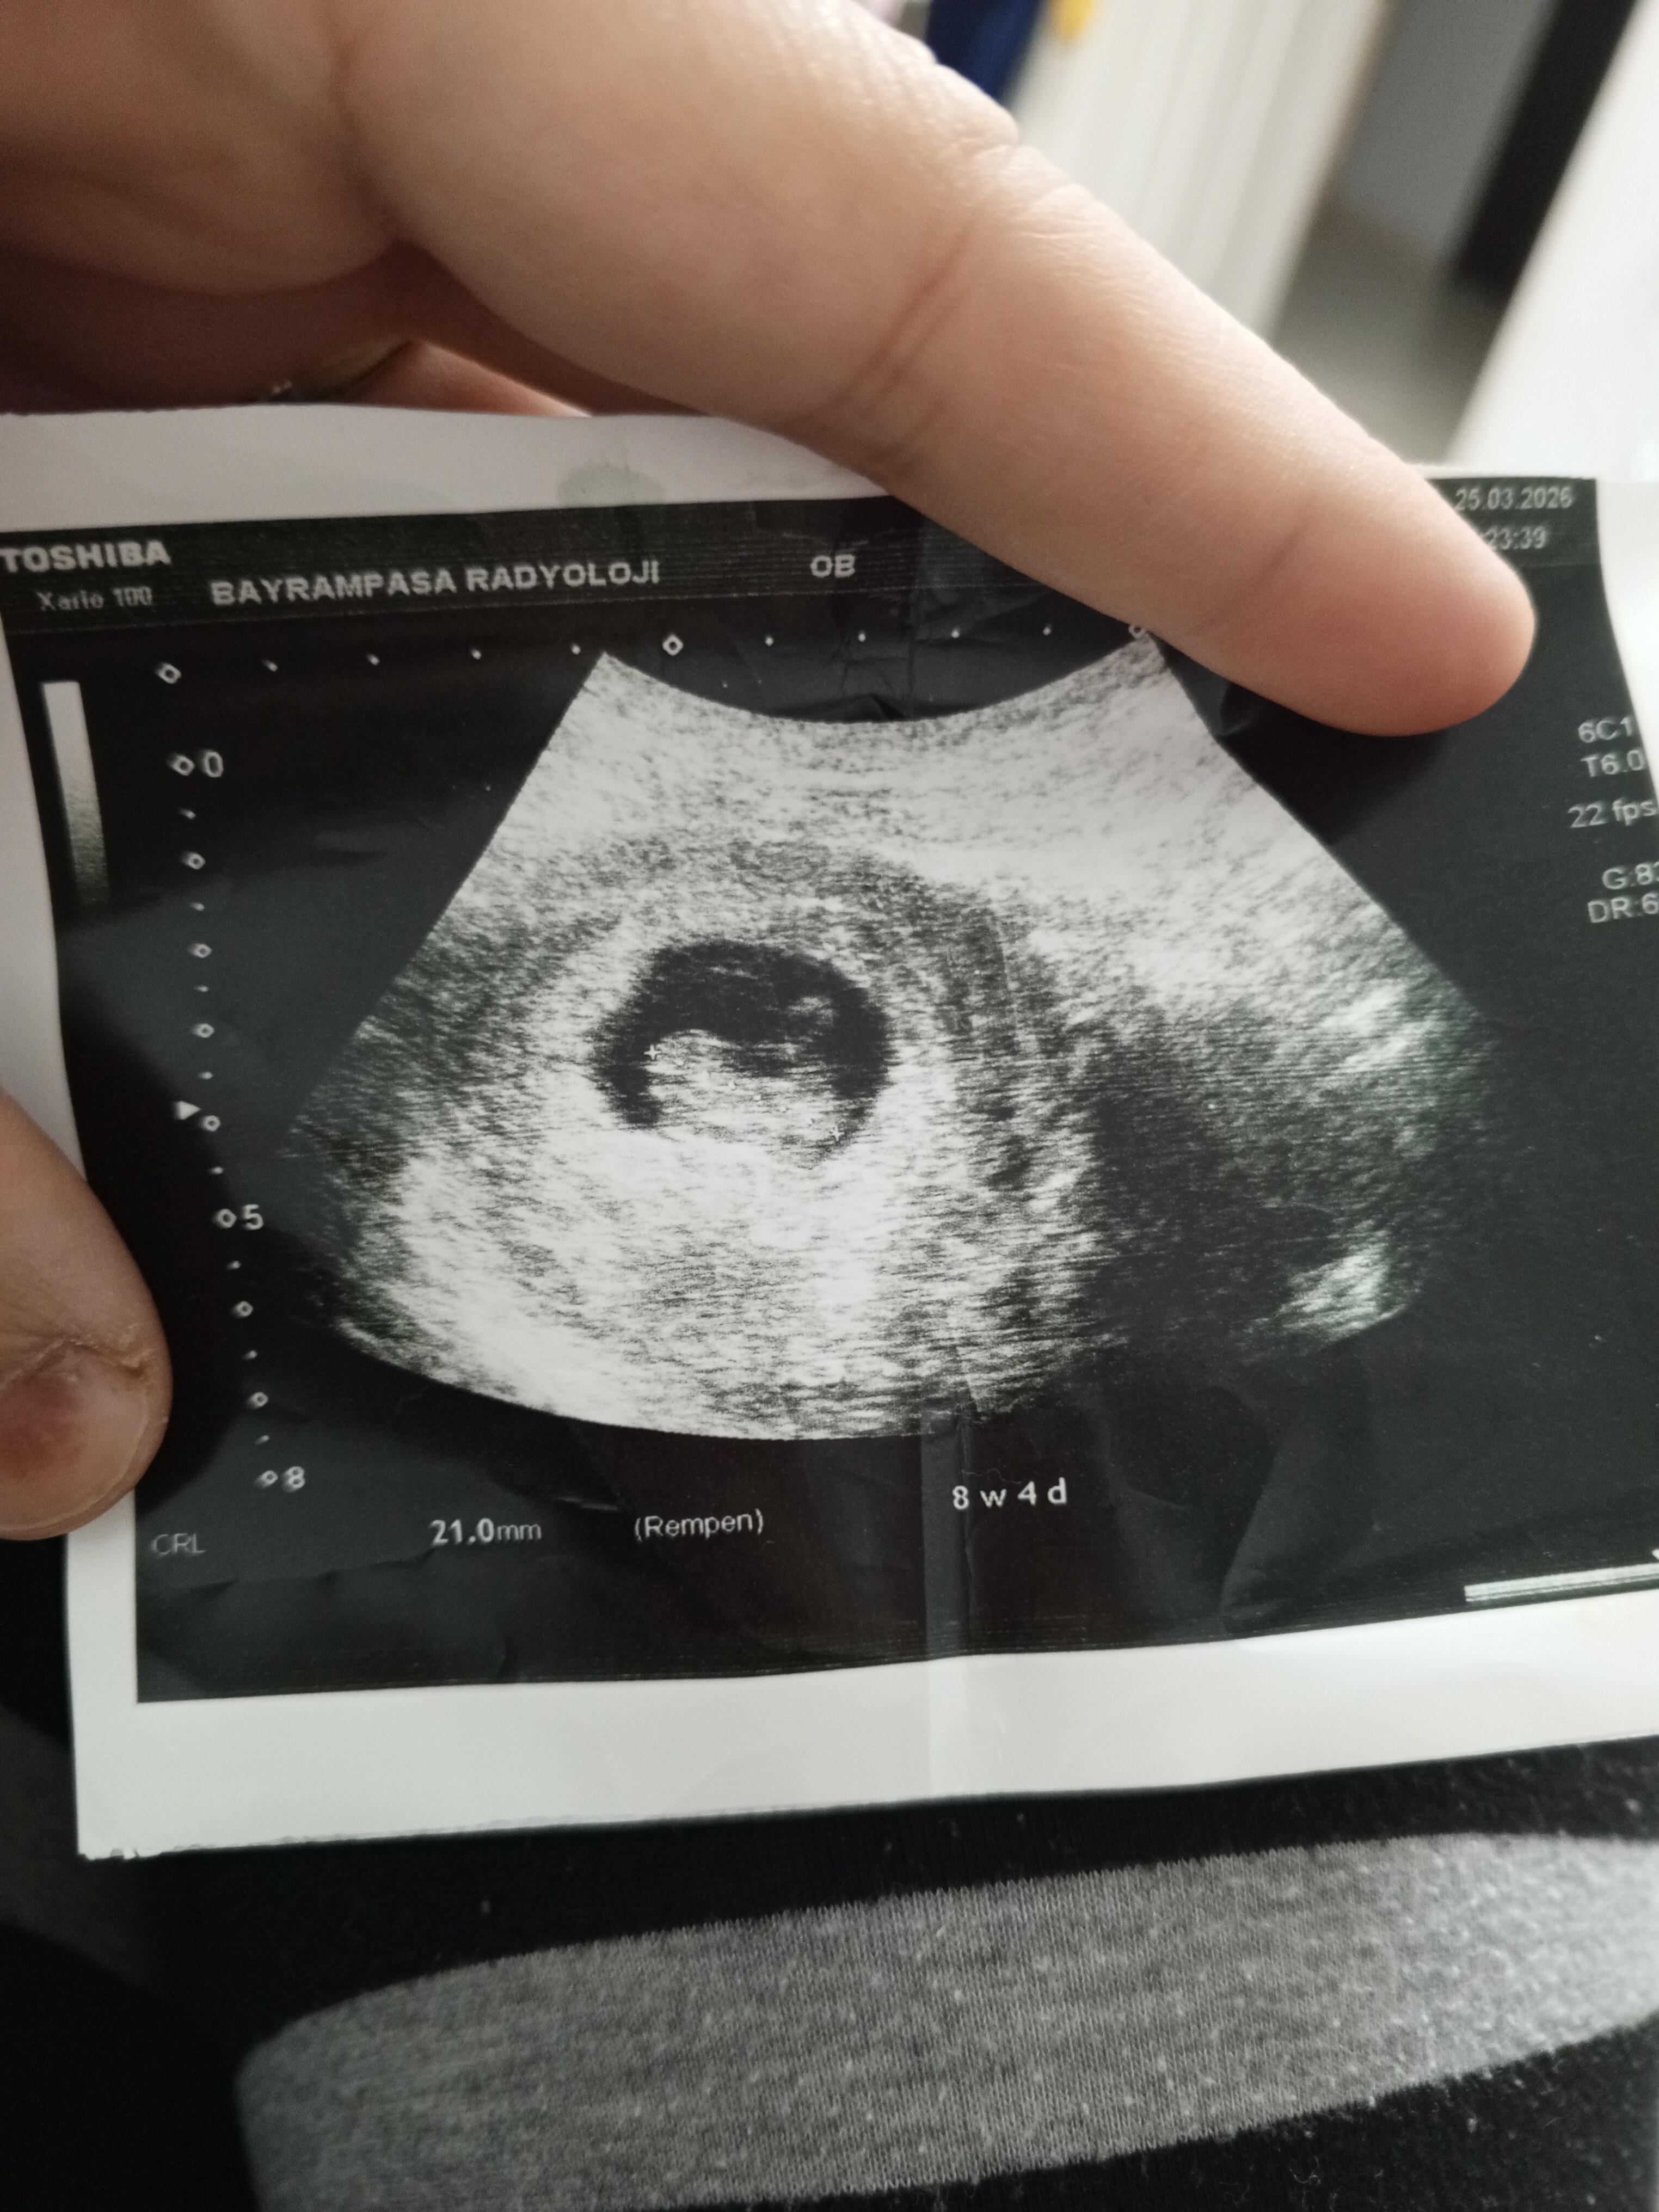

Sürekli gittiğimde erkeğe benziyor diyor doktorumuz

Ben erkek diyorum ![]()

Kız gibi sanki

Gördüm görseli, Kız gibi hissettim.

20 haftalık olmuş zaten cinsiyet söylemeleri lazım ben 14 haftalıkken öğrendim